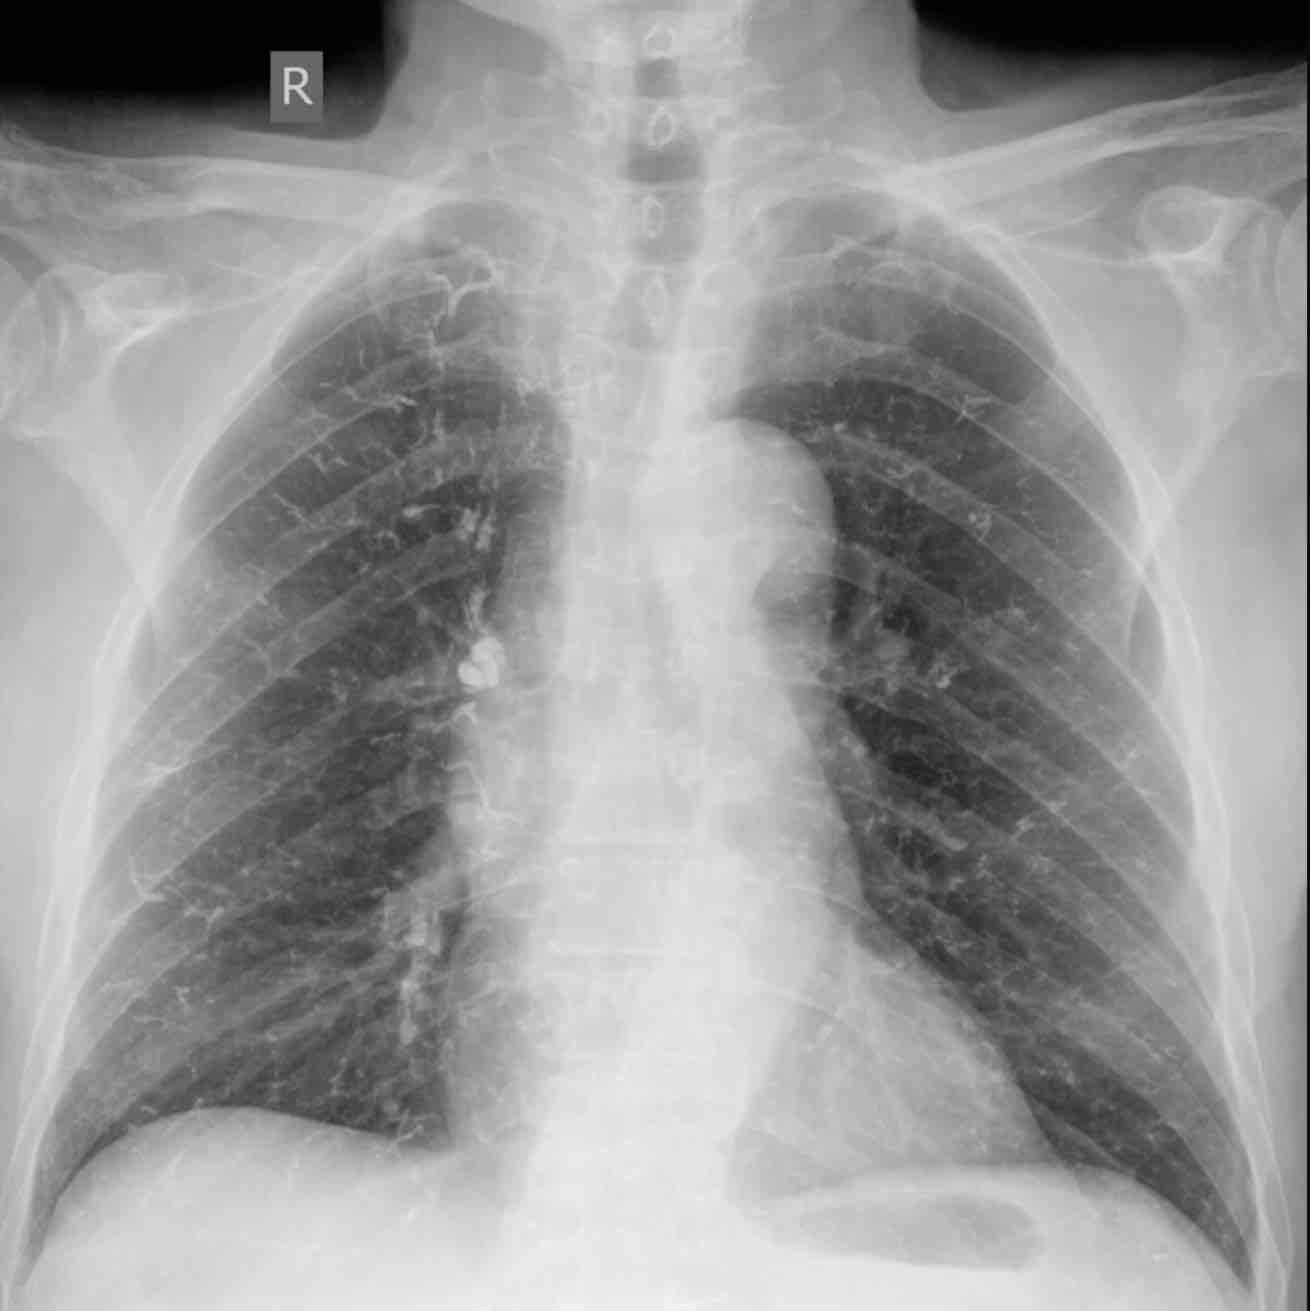

תסחיף ריאתי הוא מצב שבו קריש דם חוסם עורק בריאה, גורם למצוקה נשימתית ולעומס על הלב. זהו מצב חירום רפואי. כל עיכוב באבחון מגדיל דרמטית את הסיכון למוות או לנכות קשה.